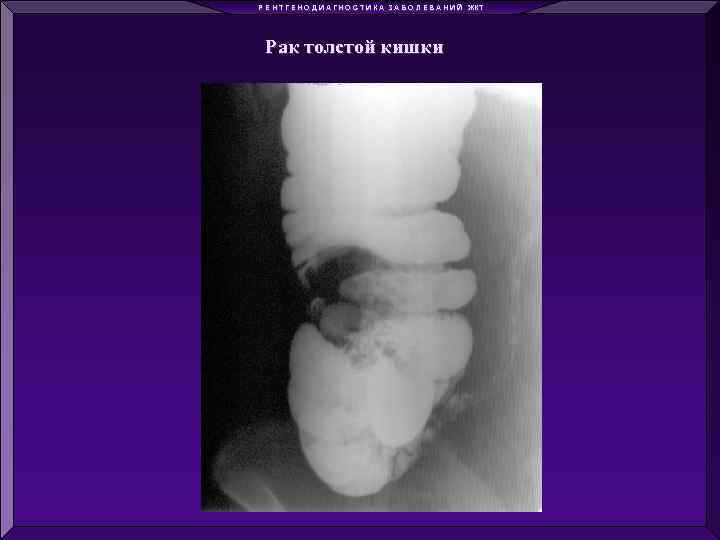

Р Е Н Т Г Е Н О Д И А Г Н О С Т И К А З А Б О Л Е В А Н И Й ЖКТ Рак толстой кишки

Р Е Н Т Г Е Н О Д И А Г Н О С Т И К А З А Б О Л Е В А Н И Й ЖКТ Рак толстой кишки

Р Е Н Т Г Е Н О Д И А Г Н О С Т И К А З А Б О Л Е В А Н И Й ЖКТ Рак толстой кишки

Р Е Н Т Г Е Н О Д И А Г Н О С Т И К А З А Б О Л Е В А Н И Й ЖКТ Рак толстой кишки

Р Е Н Т Г Е Н О Д И А Г Н О С Т И К А З А Б О Л Е В А Н И Й ЖКТ Рак толстой кишки

Р Е Н Т Г Е Н О Д И А Г Н О С Т И К А З А Б О Л Е В А Н И Й ЖКТ Рак толстой кишки